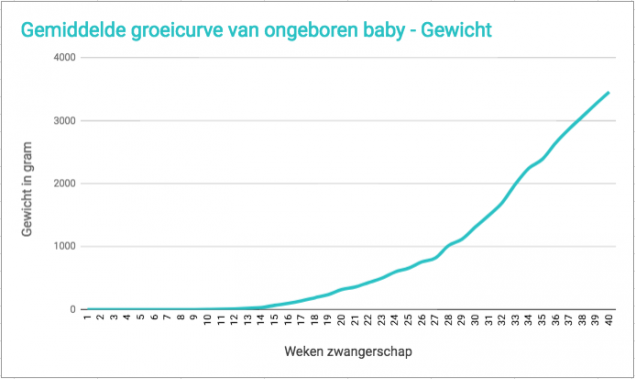

Gemiddelde Lengte En Gewicht Van Baby Tijdens Zwangerschap Babyblog

Lengte Gewicht Baby In De Buik Babytijd Com